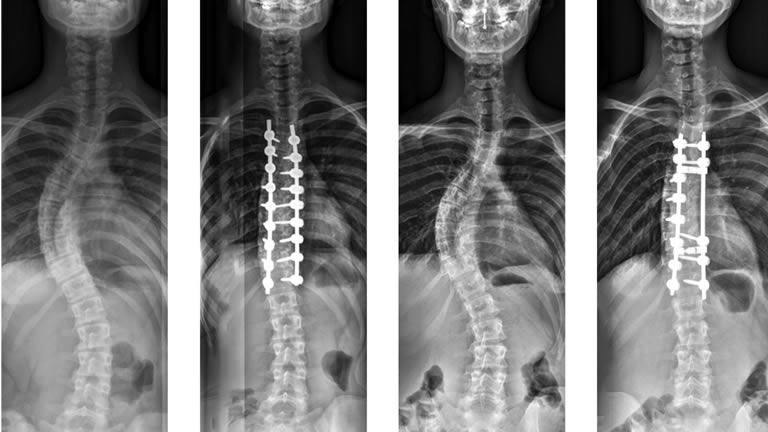

La Oferta Médica del Hospital Puebla para pacientes fóraneos brinda atención integral para Corrección de Escoliosis, donde se repara la curvatura anormal de la columna vertebral (escoliosis). El objetivo es enderezar la columna vertebral para corregir el problema en la espalda.